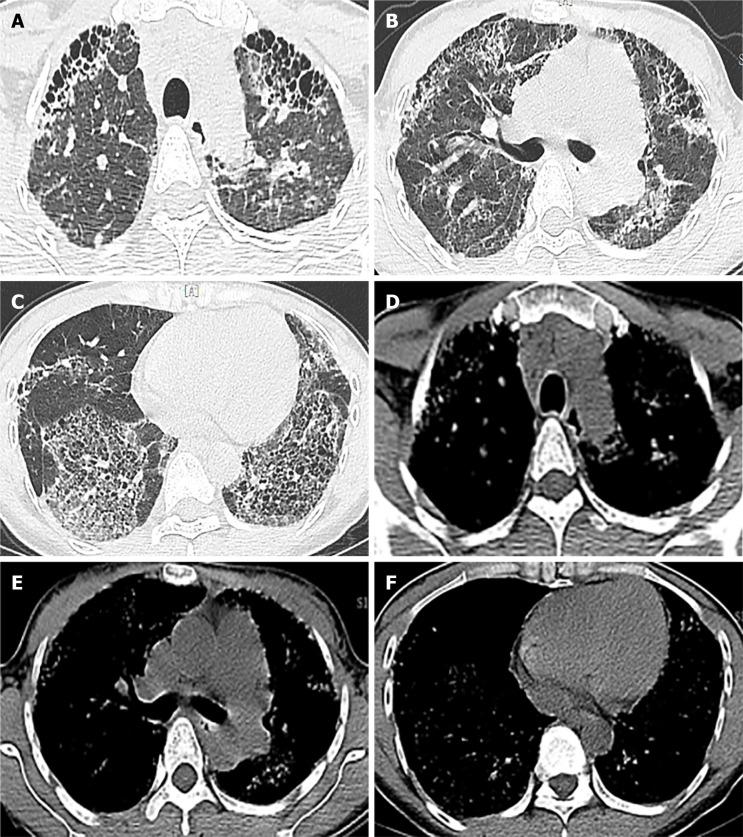

A 35-year-old female was admitted to the hospital with a cough and breathing difficulties for more than one year. She was a nonsmoker and a manufacturer of halogen dishes, which are characteristic Chinese foods, for 15 years without any protection. High resolution computed tomography of the chest demonstrated an interstitial pneumonia pattern. Pulmonary function examination showed restricted ventilation dysfunction and a significant reduction in dispersion ability. Cell differentiation in bronchoalveolar lavage fluid demonstrated lymphocytosis (70.4%) with an increased lymphocyte CD4/CD8 ratio (0.94). Transbronchial lung biopsy combined with lung puncture pathology showed diffuse uniform alveolar interval thickening, chronic inflammatory cell infiltration, a proliferation of tissue in the bronchial wall fiber and alveolar epithelial follicle degeneration, resulting in fibrosis.

一名35岁女性因咳嗽和呼吸困难入院,症状持续一年多。她不吸烟,从事卤味制作(一种具有中国特色的食品)15年,期间未采取任何防护措施。胸部高分辨率计算机断层扫描显示为间质性肺炎模式。肺功能检查显示通气功能受限和弥散能力显著降低。支气管肺泡灌洗液体细胞分化显示淋巴细胞增多(70.4%),淋巴细胞CD4/CD8比值升高(0.94)。经支气管肺活检联合肺穿刺病理显示弥漫性均匀肺泡间隔增厚、慢性炎症细胞浸润、支气管壁纤维组织增生以及肺泡上皮滤泡变性,导致纤维化。